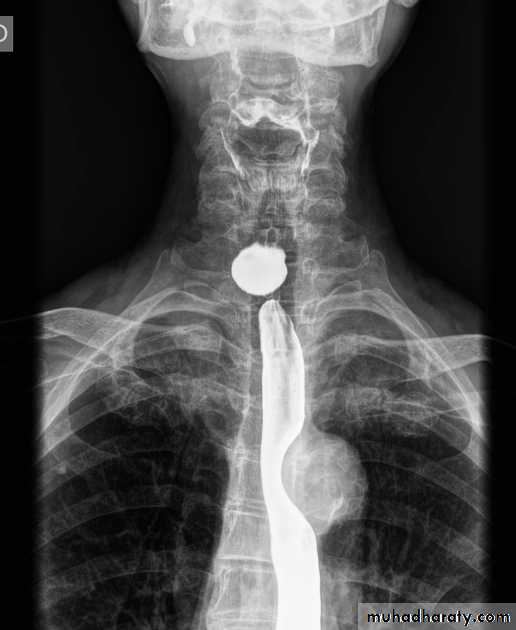

Esophageal diseases